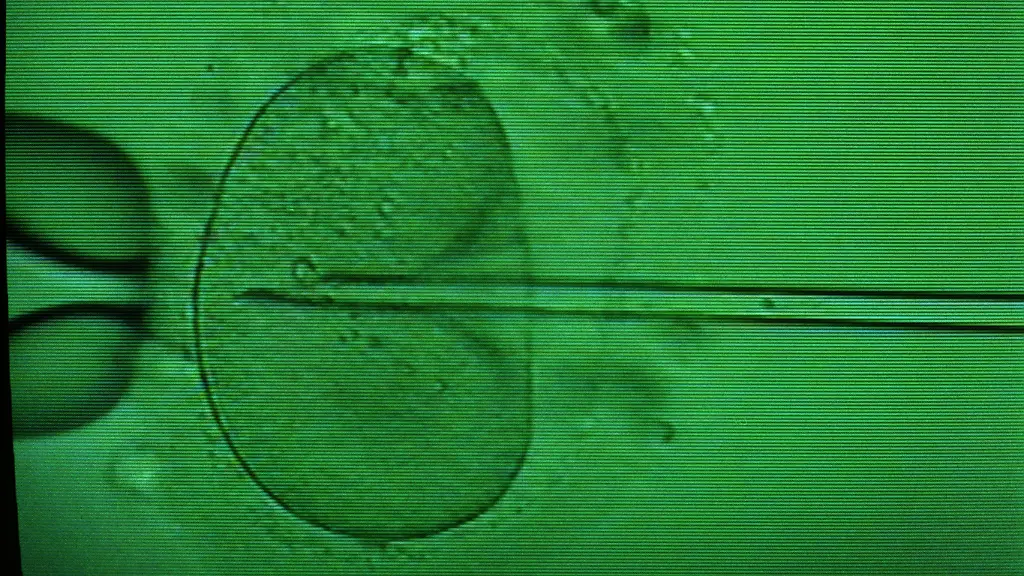

Bei der In-Vitro-Fertilisation wird in einem Reagenzglas eine Eizelle durch eine Samenzelle befruchtet. Der so gebildete Embryo wird dann in den Mutterleib eingepflanzt. Seit der Geburt des ersten Retortenbabys Louise Brown 1978 sind mehr als fünf Millionen Kinder durch diese Methode auf die Welt gekommen. In Entwicklungsländer hindern die hohen Kosten aber viele Frauen daran, die Technik in Anspruch zu nehmen. In vielen Ländern werden Frauen stigmatisiert, die keine Kinder auf die Welt bringen können.